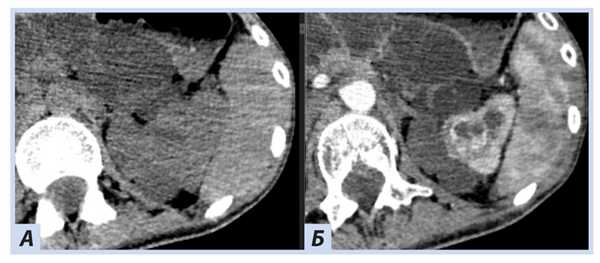

(Слева) КТ с контрастированием, аксиальная проекция: у пациента с болезнью Гиппеля-Линдау выявлены двусторонние кисты почек и множественные сложные кистозные объемные образования с контрастируемыми узелками и перегородками, что позволяет предположить кистозный ПКР. Кисты почек и ПКР - распространенные висцеральные проявления болезни Гиппеля-Линдау.

(Справа) КТ с контрастированием, аксиальная проекция: у данного пациента визуализированы множественные кисты поджелудочной железы.

(Слева) КТ с контрастированием, аксиальная проекция: у пациента с болезнью Гиппеля-Линдау выявлены множественные двусторонние кисты почки и ПКР. Выявлено кистозное новообразование в головке поджелудочной железы. Поджелудочные проявления болезни Гиппеля-Линдау включают кисты, кистозные новообразования (микрокистозная аденома) и нейроэндокринные опухоли.

(Справа) МРТ, постконтрастное Т1-ВИ, аксиальная проекция: выявлены множественные контрастируемые патологические изменения мозжечка, что позволяет предположить гемангиобластомы.